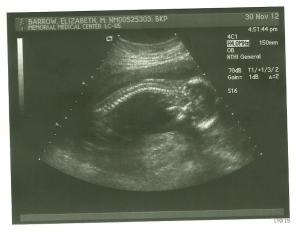

During the ultrasound I laid there praying that all fingers and toes were there and wouldn’t even look at the monitor. She finally confirmed that to me and then turned the monitor towards me and this was the position I saw. She just wanted to dangle there and hang out. The tech was trying to find out the gender for me but the baby’s legs were all crossed.